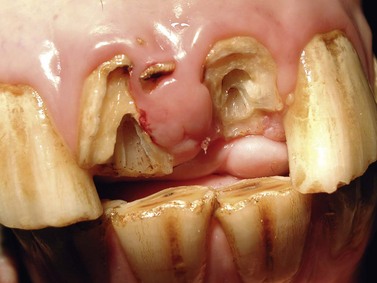

Initially, loose dental fragments are removed from fractured teeth (Fig. 22.2), and then 2–3 mm of the clinical crown should be removed if the affected tooth is still in occlusal contact, to avoid occlusal pressure from the opposing teeth for a minimum of 2–3 months.1 Bleeding resulting from these procedures can be controlled using locally applied hemostyptic drugs (e.g., adrenaline) or electrosurgical devices.

image

Fig. 22.2 Contaminated traumatic fractures of 202, and 203.